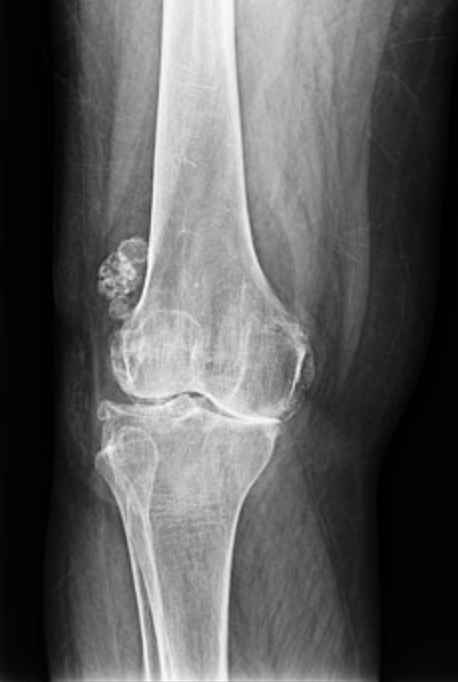

據(jù)統(tǒng)計,目前全世界關節(jié)炎患者有3.55億人,在亞洲,每6個人中就有1人患上關節(jié)炎這種頭號致殘疾病,它并非只是老人的“專利”,所有年齡段的人,甚至包括兒童都有可能罹患此病。關節(jié)炎在我國的總發(fā)病率約為13%,目前已超1億患者,而且有年輕化的趨勢,但它的診治情況并不樂觀,據(jù)中國類風濕關節(jié)炎直報項目數(shù)據(jù)顯示,我國類風濕關節(jié)炎患者從出現(xiàn)癥狀至明確診斷的平均時間間隔在2年以上,提示大多數(shù)患者未得到及時和早期診斷,錯過了早期治療的最佳時機。對關節(jié)炎要早預防、早診斷、早治療,防止致殘?!凹t、腫、熱、痛”四點自測是否患上關節(jié)炎關節(jié)炎可在各個關節(jié)發(fā)病,除膝關節(jié)外,手指關節(jié)、髖關節(jié)、趾關節(jié)、脊柱關節(jié)等也是易發(fā)部位。那么如何判斷自己有無關節(jié)炎呢?戴冽教授介紹,首先可以根據(jù)關節(jié)有無紅、腫、熱、痛以及功能障礙來進行判斷?!凹t”是指關節(jié)急性炎癥時會出現(xiàn)皮膚發(fā)紅?!澳[”是指因關節(jié)腔內(nèi)積液或關節(jié)周圍軟組織炎癥引起關節(jié)腫脹?!盁帷笔侵刚H说年P節(jié)摸起來是涼的,如果關節(jié)部位摸起來是熱的甚至發(fā)燙,那么就證明關節(jié)有炎癥存在?!巴础笔顷P節(jié)炎的最主要表現(xiàn),多在活動時出現(xiàn),有些疾病可在休息時出現(xiàn),炎癥明顯時外力壓迫疼痛加劇?!肮δ苷系K”是指關節(jié)腫痛或結構破壞導致活動受限。常見的關節(jié)炎有四種,分別是:骨關節(jié)炎、類風濕關節(jié)炎、強直性脊柱炎和痛風,這四種關節(jié)炎各有不同的特點:骨關節(jié)炎是一種退行性骨關節(jié)病,多見于50歲以上者,因此被稱作“中老年人致殘殺手”。骨關節(jié)炎主要累及膝、脊柱等負重關節(jié)。通常表現(xiàn)為上下樓梯、蹲起時感覺膝蓋疼痛不適,早晨起床或久坐后膝蓋感覺發(fā)僵。隨病情加重,患者可能會有平地走路疼痛,甚至關節(jié)變形等癥狀。類風濕關節(jié)炎常見表現(xiàn)是雙手指、腕、肘、膝、踝、足部關節(jié)對稱性疼痛,常伴有早晨起床時關節(jié)僵硬感,未經(jīng)規(guī)范治療常出現(xiàn)關節(jié)畸形,嚴重影響工作和生活。80%發(fā)病于35-50歲的中青年,女性多見,因此是“中青年女性致殘殺手”。強直性脊柱炎主要侵犯脊柱,多見于青壯年男性,是“青年男性致殘殺手”。主要表現(xiàn)為夜間及早晨起床時腰痛,也可出現(xiàn)非對稱性的下肢大關節(jié)炎,未經(jīng)治療出現(xiàn)脊柱畸形,嚴重影響生活質(zhì)量。多有家族史,90%以上患者HLA-B27陽性。痛風是長期高尿酸血癥后尿酸鹽晶體在關節(jié)沉積誘發(fā)關節(jié)炎,疼痛劇烈、紅腫明顯,初期可自然消退。間斷發(fā)作,如不治療轉化為慢性痛風石性關節(jié)炎后則變成持續(xù)性疼痛。除引起關節(jié)畸形外,痛風還可以引起腎功能不全、高血壓、冠心病、腦卒中等。痛風現(xiàn)已成為常見病,多見于成年男性和老年女性。彭統(tǒng)華教授提醒,關節(jié)炎種類繁多,一般人通常難以準確辨別,因此出現(xiàn)關節(jié)疼痛和病變時建議用手機拍下當時關節(jié)情況,并及時到正規(guī)醫(yī)療機構進行診治,讓醫(yī)生為您提供專業(yè)的治療建議,以免耽誤病情,造成不可逆的損傷。

當患者骨關節(jié)炎OA受累關節(jié)有比較明確的關節(jié)腔內(nèi)游離體或骨贅形成,導致關節(jié)活動因交鎖或卡壓受限時,尤其適合關節(jié)鏡手術。本文系魯昕版權所有,未經(jīng)授權請勿轉載。